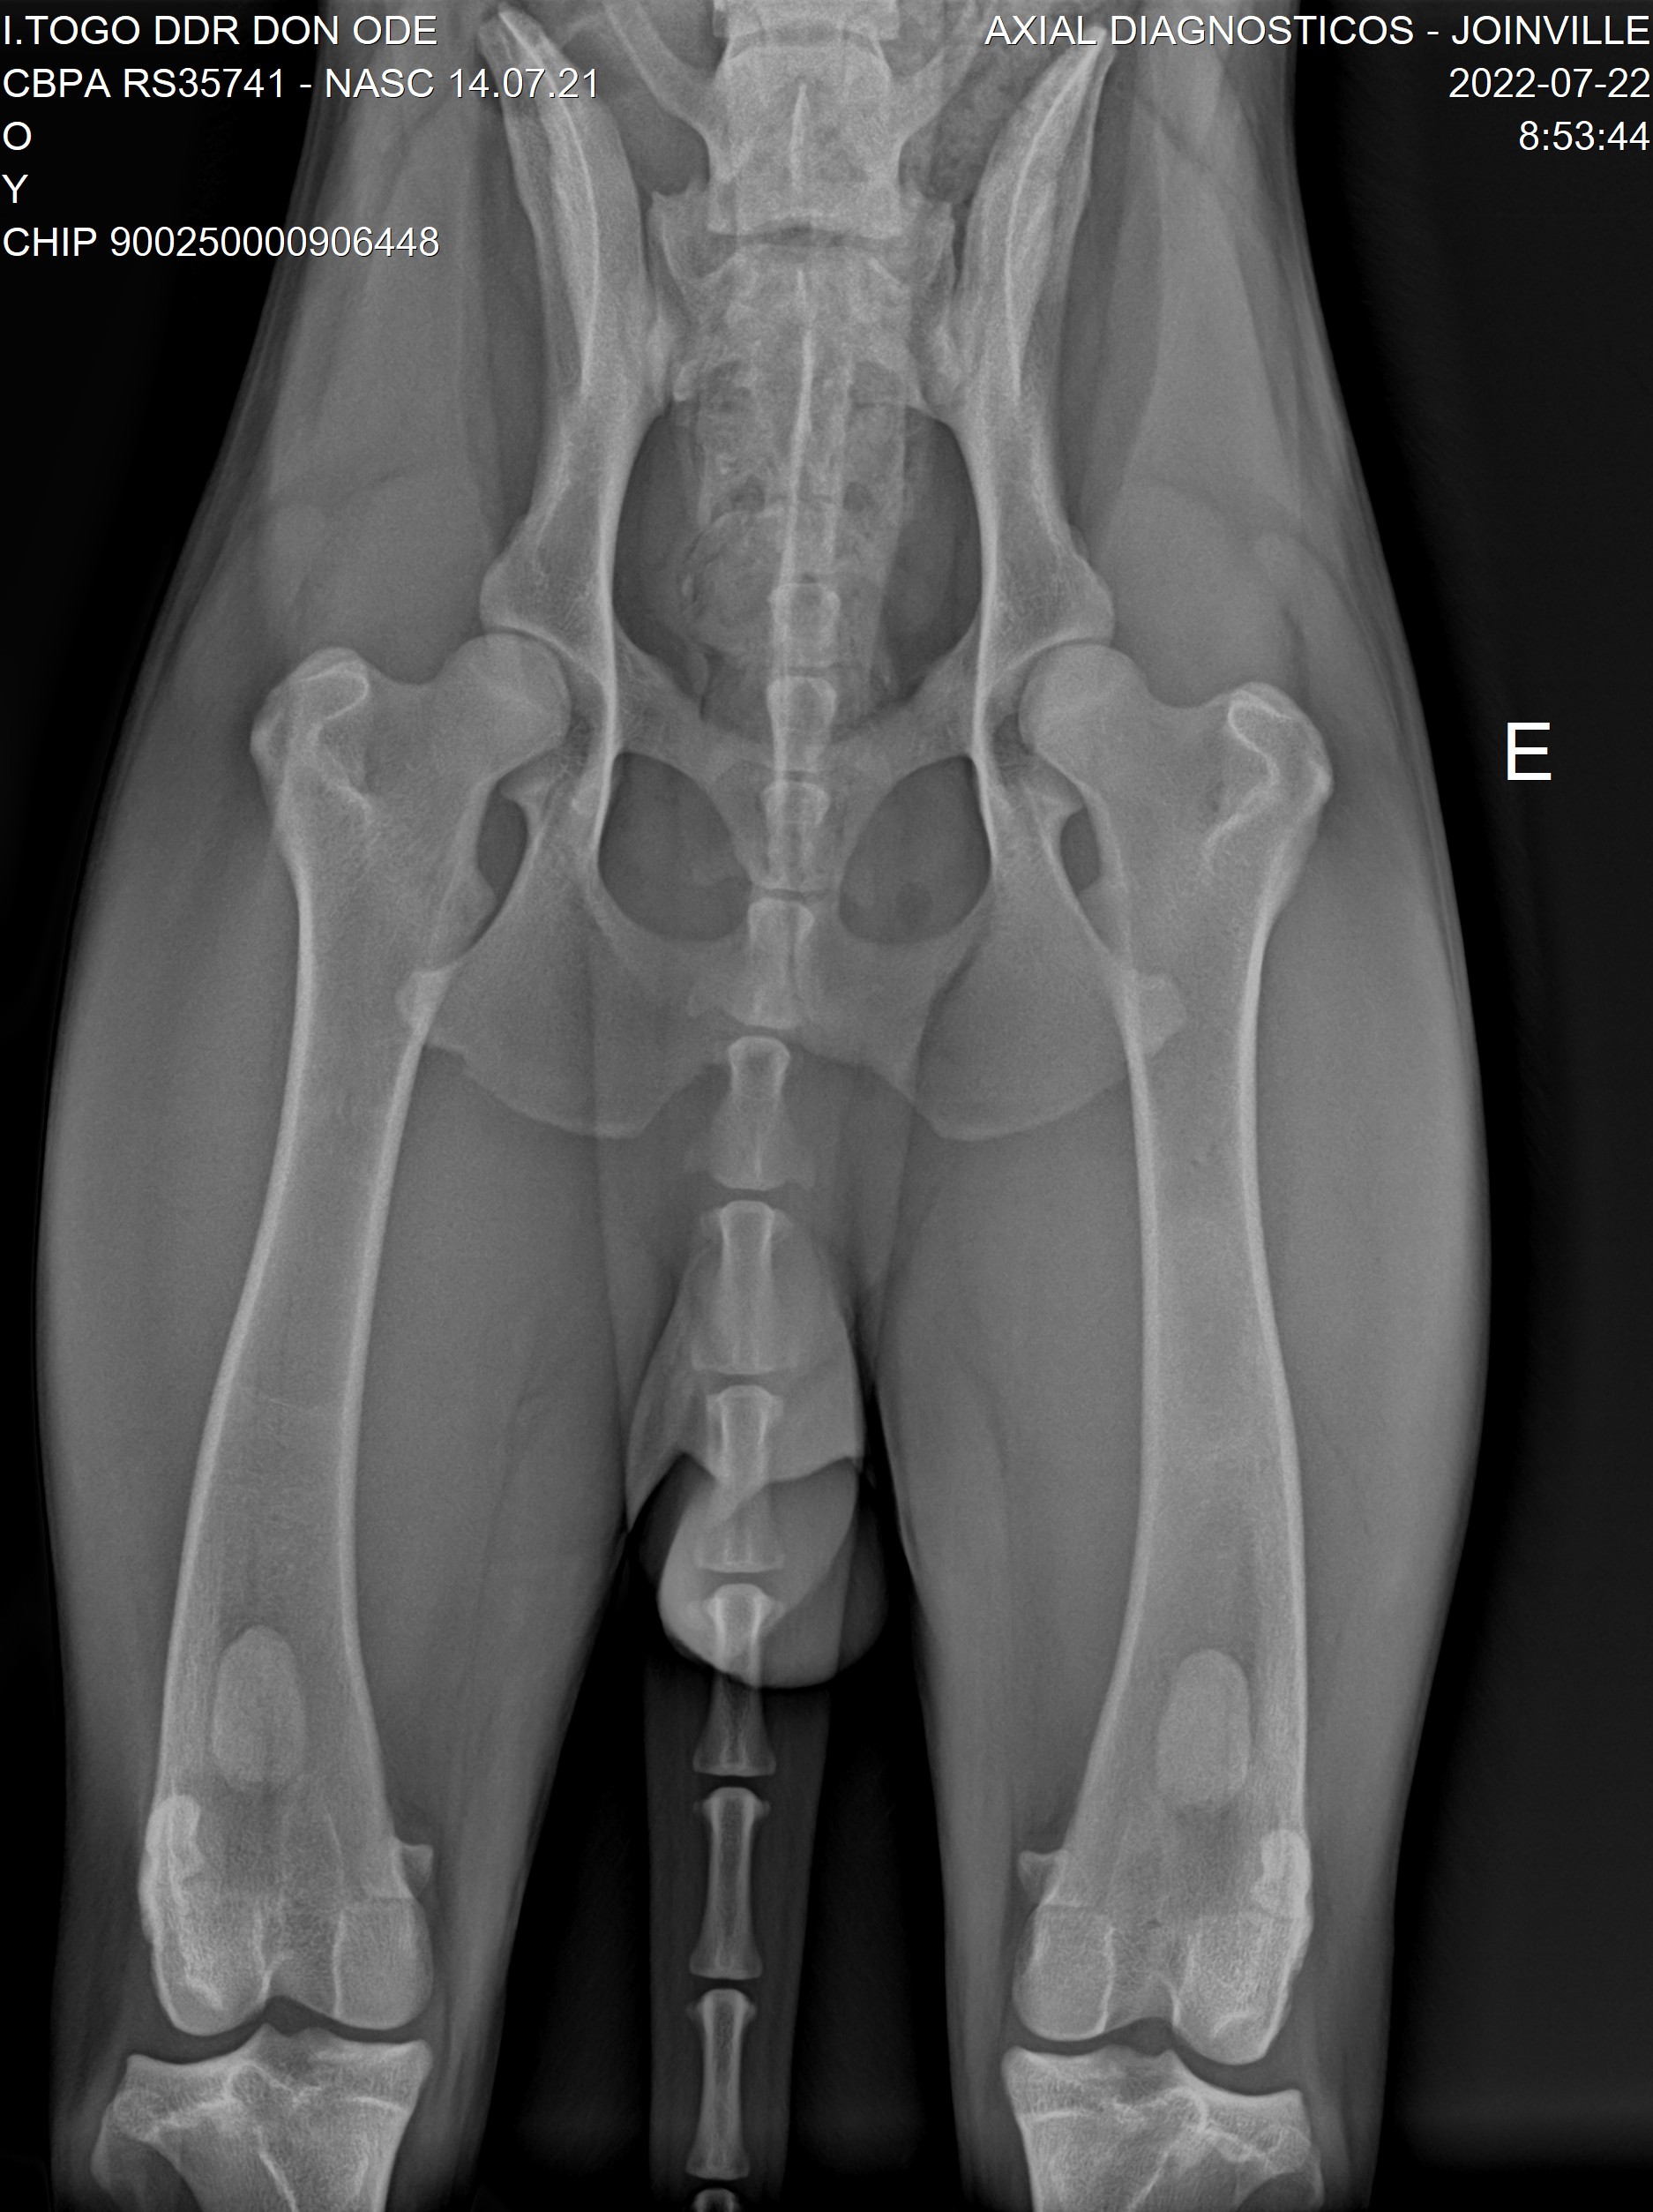

Raio X